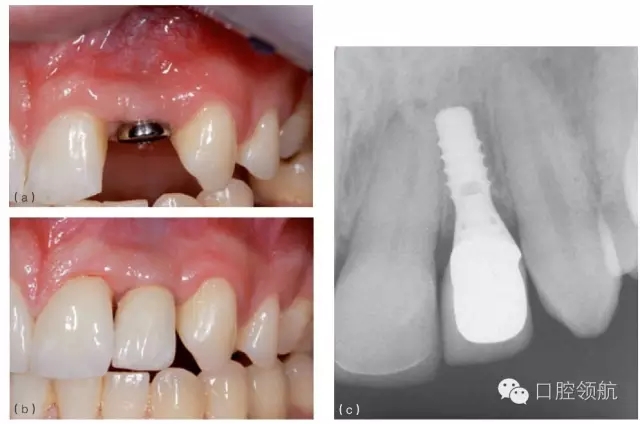

若不恰當(dāng)?shù)剡x擇了一個(gè)平臺(tái)直徑過(guò)大的種植體,有時(shí)候也可以通過(guò)仔細(xì)預(yù)備肩臺(tái)來(lái)減少平臺(tái)直徑。這僅適用于軟組織水平種植體(圖8.21a~c)?;谶@些種植體的設(shè)計(jì)特點(diǎn),肩臺(tái)直徑只能減少大約不超過(guò)0.5mm。因此減小肩臺(tái)近遠(yuǎn)中方向直徑的可能性是有限的。

圖8.21 (a)種植體安裝修復(fù)平臺(tái)后,顯示其直徑對(duì)于左上頜側(cè)切牙(10號(hào)位點(diǎn))的間隙來(lái)說(shuō)太大。注意種植體接近鄰牙,齦乳頭變平。種植體還有冠根向植入位置不佳,即植入過(guò)淺。(b)10號(hào)位軟組織水平的種植體,其肩臺(tái)鄰面和唇面可以少量選磨,最終使冠就位,注意齦乳頭變平。(c)選磨肩臺(tái)后,冠就位的X線片。